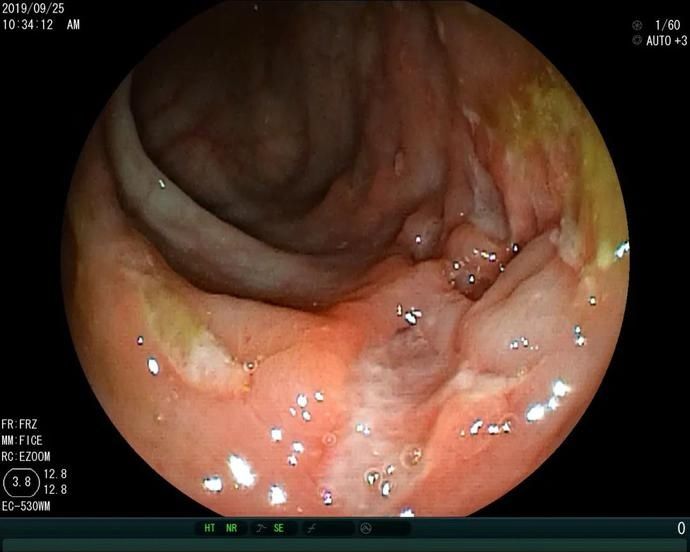

既往案例治疗前(左)后(右)对比